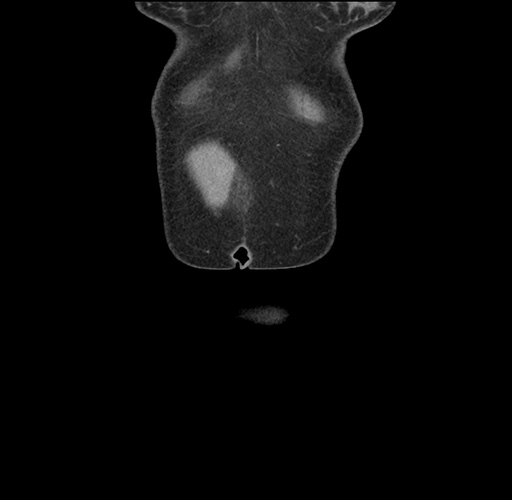

Imaging Analysis

Look through the patient's CT scan to identify any areas of concern for the necessary procedure.

Based on your CT findings, which issue(s) would give reason for "planned slowing down moment(s)" in this case?

Considering a standard left lateral sectionectomy procedure, what step(s) of the operation would you do differently in this case ?